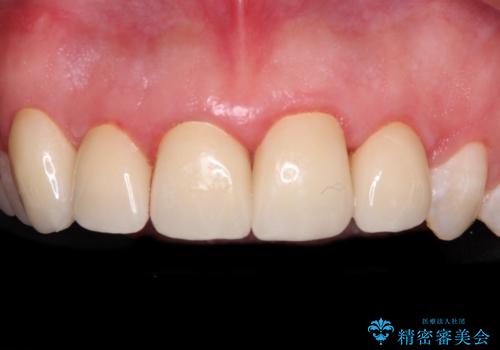

金属の裏打ちを用いたセラミッククラウンであったため歯肉縁に黒ずみが見えてくることは良くありますが、全体的に歯列が不揃いであることが気になったので、それらをオールセラミッククラウンにて改善することとしました。

オールセラミッククラウン装着後、レントゲン写真より精度良く装着されていることは確認できているので、日頃のブラッシングで改善させるよう指導しています。